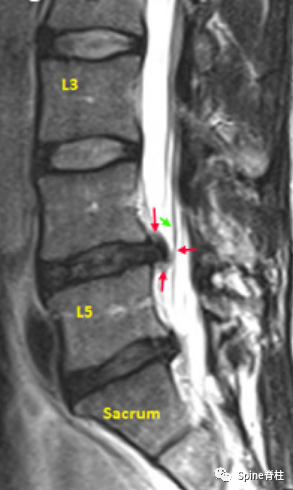

腰椎MRI旁矢状位(Para-Sagittal Region),在硬膜囊内可见走行根(红色箭头),但L5除外,它已从硬膜囊出芽(第3个红箭头)

腰椎MRI旁矢状面(侧隐窝)可见L4-5椎间盘突出(红色箭头),接触到一个走行根,甚至将其推得有点偏离轨道(绿色箭头)